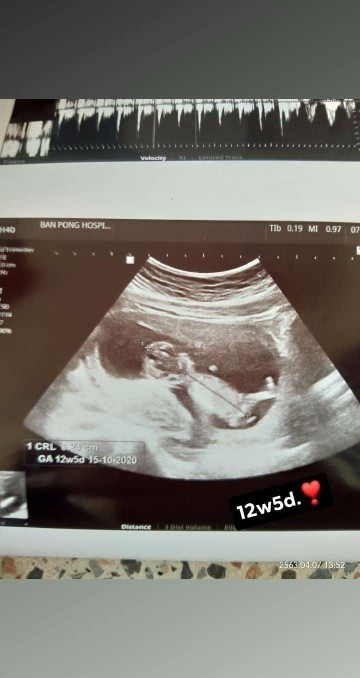

12w 5d❣️❣️

12w